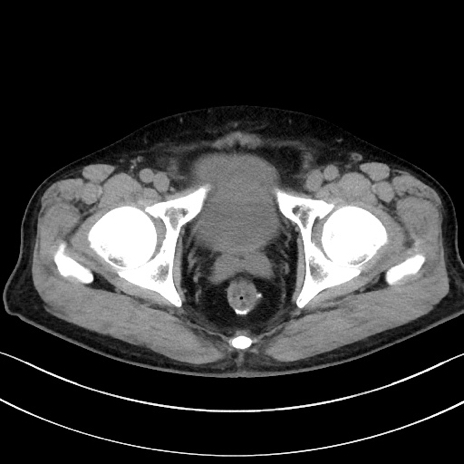

冠状断像